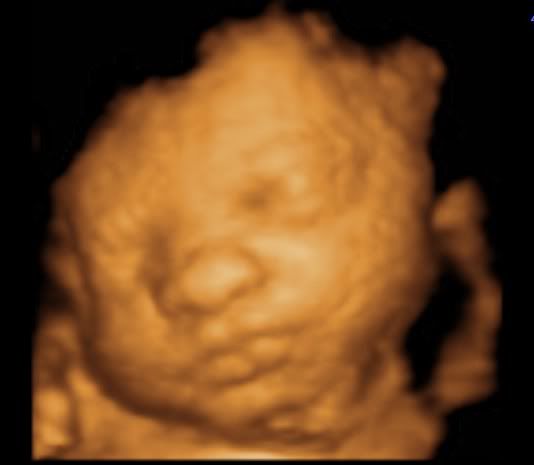

hegejenta30 Skrevet 19. mars 2011 #1608 Skrevet 19. mars 2011 Så herlige bilder av lille frøken krek! Skjønner godt du er forelsket!

Kokos Skrevet 19. mars 2011 #1611 Skrevet 19. mars 2011 Så fine bilder dere fikk! Der ser man jo vakre lille krek kjempegodt

^^Belle^^ Skrevet 19. mars 2011 Forfatter #1612 Skrevet 19. mars 2011 Så herlige bilder av lille frøken krek! Skjønner godt du er forelsket! Det gjør jeg også. Hun er jo det fiiiineste i hele verden. OOOOH, been there!!! Min var 56 cm lang da han ble født, så du kan jo tenke deg hvor deilig det var for ribsa på slutten.... Det kan jeg tenke meg. Håper ikke lille krek er så lang altså. Nusselige bilder! Takk. Så fine bilder dere fikk! Der ser man jo vakre lille krek kjempegodt Ja, noen av dem ble kjempefine. Nå gjenstår det bare å se om hun ligner på disse bildene når hun kommer ut.

Mazilla Skrevet 19. mars 2011 #1616 Skrevet 19. mars 2011 Jeg må ærlig innrømme at jeg synes alle 3D-ultralydbilder ser like ut.. Men ikke mindre koselig av den grunn, da! Kos deg i kveld! Selvfølgelig er det lov med sørlandschips på en lørdag!

^^Belle^^ Skrevet 19. mars 2011 Forfatter #1618 Skrevet 19. mars 2011 Jeg må ærlig innrømme at jeg synes alle 3D-ultralydbilder ser like ut.. Men ikke mindre koselig av den grunn, da! Kos deg i kveld! Selvfølgelig er det lov med sørlandschips på en lørdag! det har jeg også syntes frem til nå. Men vissheten om at det er vår jente vi ser...åh, jeg kan ikke la være å smile hver gang jeg ser bildene. Støttes! Og spretter i en pose med sørlandschips med spansk paprika! *mmmm* sørlandschips er bare best.

Småkjekset Skrevet 19. mars 2011 #1619 Skrevet 19. mars 2011 29 uker Så skjønn og fredfull hun ser ut Håper du får en fantastisk kveld med god snacks

Neala Skrevet 20. mars 2011 #1620 Skrevet 20. mars 2011 Åh, i alle dager, så fin hun ser ut! Tenker dere ikke gleder dere noe mindre nå